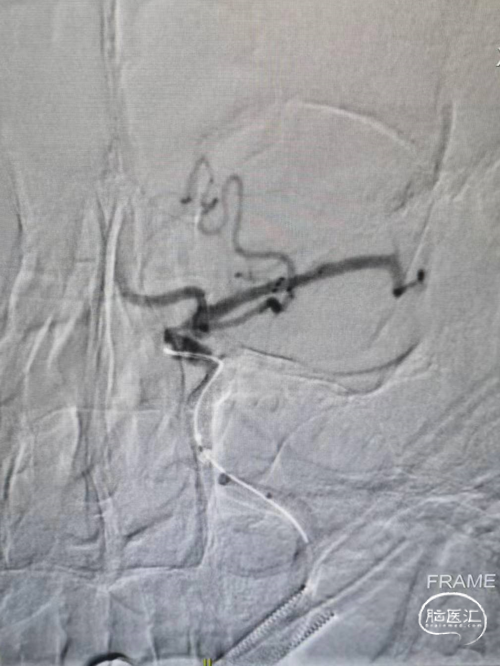

➢术后即刻影像

术后颈内动脉末端血流通常,左侧大脑前动脉和大脑中动脉显影正常。

此病例是一个常见的颈内动脉急性闭塞的病变,相信绝大多数开展介入治疗的医院也做过很多相似病例。术中亮点是使用了负压抽吸,防止血栓的逃逸;其次是器械的选择,选择太小的支架可能无法达到一次再通。本病例选择RECO取栓支架 6*30cm,释放之后径向支撑力大,能够应对颈内末端比较粗的血管,并且卷曲的设计也能防止对大脑中动脉的损伤。